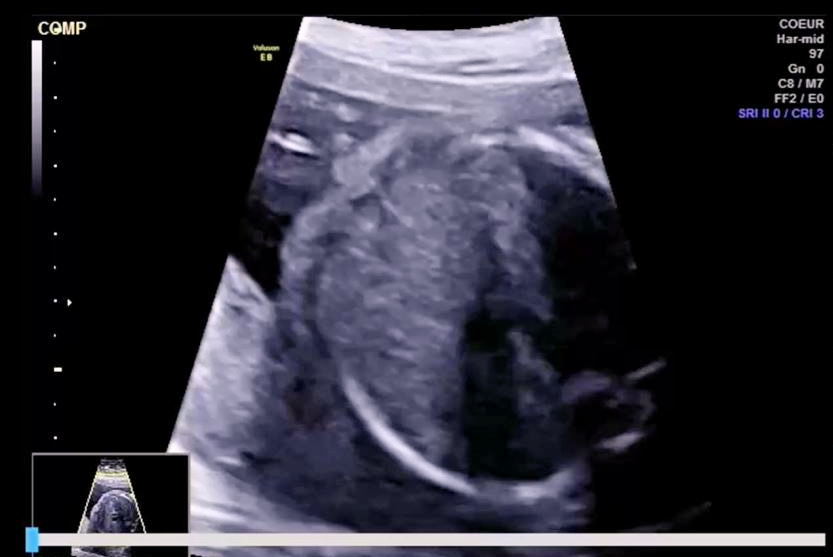

The company debuted Samsung Z20 at the Society for Maternal-Fetal Medicine (SMFM) 2025. The system features Live ViewAssist, a real-time deep learning tool that enhances precision and simplifies advanced obstetrical exams, according to the firm. Its other capabilities include automatic identification and labeling, real-time quality evaluation, and measurements.